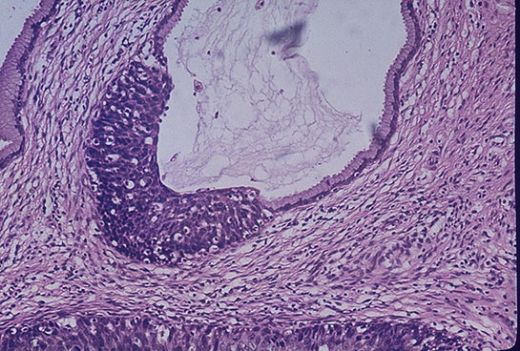

1. Squamöz Epitel Hücreleri: Genellikle mesane ve üretra gibi alt idrar yollarında bulunur. Bu hücreler, idrar yolu enfeksiyonlarına veya irritasyona işaret edebilir. 2. Transisyonel Epitel Hücreleri: Mesane duvarını kaplayan bu hücreler, mesanenin dolup boşalma sırasında şekil değiştirme yeteneğine sahiptir. Transisyonel epitel hücrelerinin varlığı, mesane ya da böbrek hastalıklarını gösterebilir. 3. Silindirik Epitel Hücreleri: Bu hücreler, genellikle böbreklerde bulunur ve böbrek hastalıklarının tespitinde önemli olabilir. Klinik Anlamı İdrarda epitel hücrelerinin varlığı, çeşitli klinik durumlarla ilişkilidir. Özellikle idrar tahlilinde epitel hücrelerinin sayısı ve tipi, aşağıdaki durumlar için önemli ipuçları sunabilir: